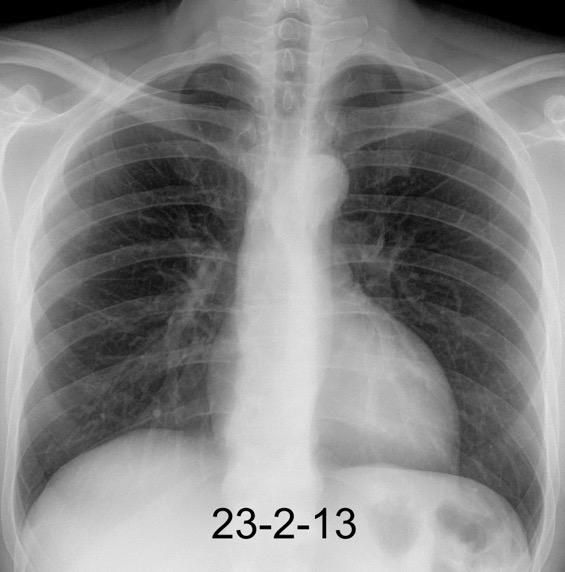

30 años

Borramiento de la banda PARA-aórtica por AdenoCa. de LII, no visible en 2005

Colapso de LII. TC: secreciones bronquiales.

Endoscopia tapón mucopurulento extraído

Borramiento parcial por Ca. epidermoide.